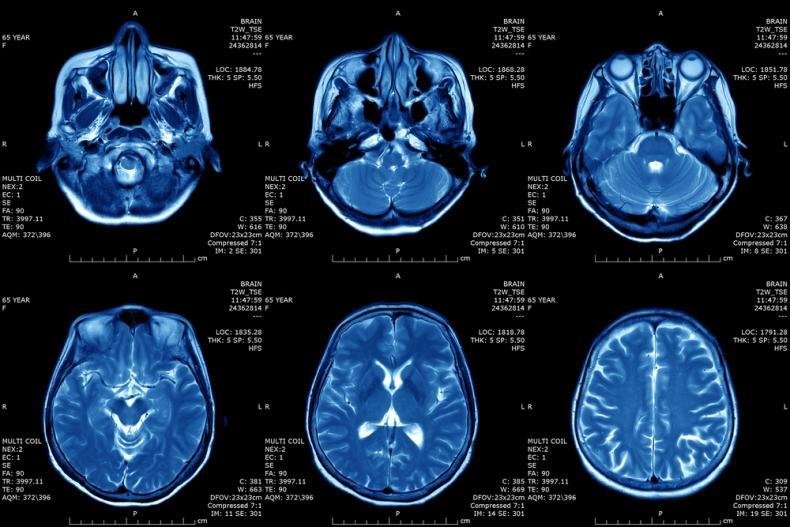

Магнитно-резонансная томография (МРТ)

Принцип МРТ основывается на свойстве ядер атомов реагировать на сильное магнитное поле. Расчёт идёт на реакцию ядер водорода, которых много в составе молекул воды, а тело человека, как известно, на 60% состоит из воды. Попадая в магнитное поле, ядра атомов ориентируются вдоль него, их можно возбуждать и фиксировать энергию, которые они будут отдавать при ослаблении воздействия, т.е. “расслаблении”. Компьютерный анализ позволяет преобразовать полученную информацию и определить расположение, плотность и структуру тканей в организме.

МРТ позволяет “разглядеть” хрящи, мягкие ткани и мозг человека, при этом не оказывая вредного воздействия, поэтому процедуру можно проводить всем и сколько угодно раз. Однако исследование занимает много времени, кроме того, томографы закрытого типа могут вызывать приступы клаустрофобии. Правда, есть аппараты открытого типа. Нельзя проводить процедуру МРТ людям, у которых в тело вживлены электроприборы (например, кардиостимуляторы) или металлические имплантаты.

МРТ будет эффективно при исследовании опухолей, мозга и аномалиях развития сосудов.

мрт снимок